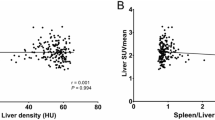

The mean SUVmax of the liver in the control group (5.48 ± 2.3) was significantly lower than the SUVmax of the steatosis group (7.96 ± 2.0; P < 0.001; Fig. 2). The mean SUVl/b in the steatosis group was significantly higher as compared to the control group (7.17 ± 1.7 vs. 4.78 ± 2.2; P < 0.001). Increasing SUVmax of the liver had a statistically significant negative correlation with decreasing mean HU (r = − 0.52; P < 0.001). The SUVl/b and the HU liver showed a significant correlation, too (r = − 0.59; P < 0.001). This relationship is shown in Fig. 3.

For further analysis, we excluded all patients with a borderline HU value of the liver between 40 and 45 (n = 13). We aimed for a more robust differentiation of patients and tried to exclude patients with borderline fatty involvement of the liver. In the remaining patients, SUVmax (7.96 vs. 4.89; P < 0.001) and SUVl/b (7.17 vs. 4.27; P < 0.001) of the steatosis group was significantly higher as compared to the control group. HU of the liver and SUVmax (R = − 0.60; P < 0.001) and SUVl/b (R = − 0.57; P < 0.001) correlated significantly. Using ROC analysis SUVmax had a sensitivity of 94% with a specificity of 82% (AUC = 0.89; threshold SUVmax 5.86). SUVl/b had a sensitivity of 100% and a specificity of 80% (AUC = 0.91, threshold SUVmax 5.08) (Fig. 4).